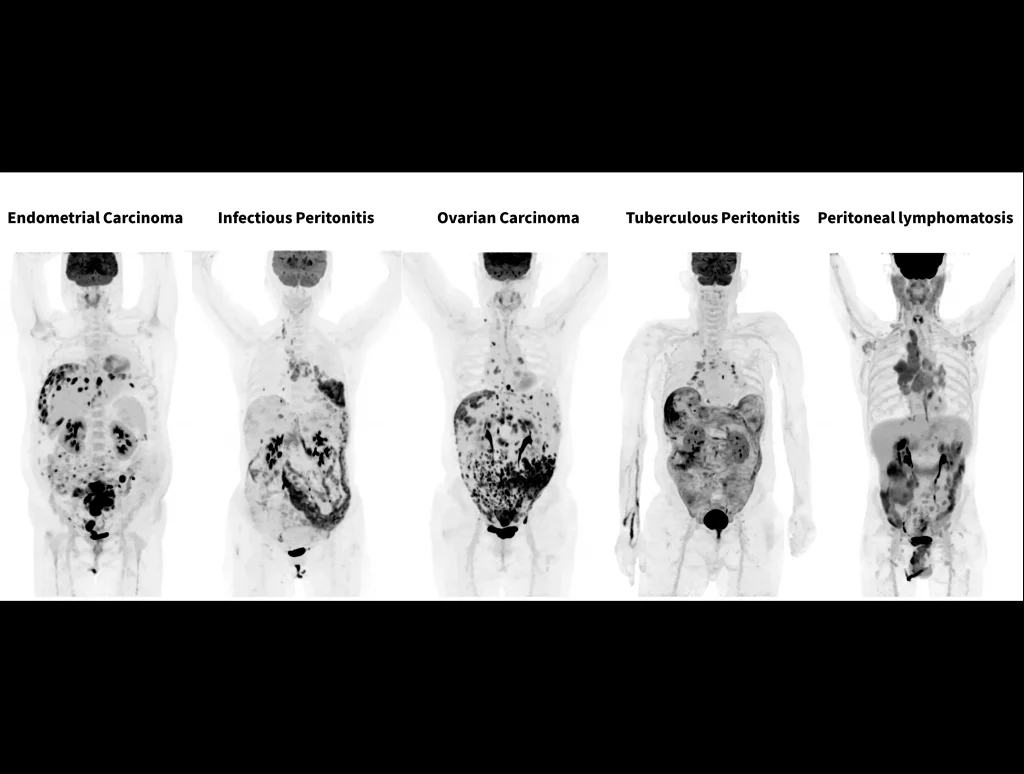

With the ultra-high system performance, uMI Panorama faces up to the challenges of tracers with different half lives and the complex scanning conditions, without compromise for image quality.

Case Gallery